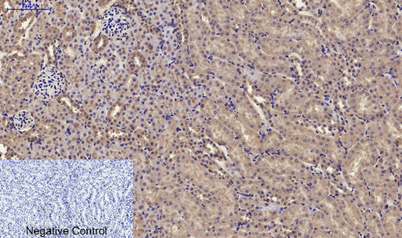

Product name: RANKL rabbit pAb

Dilutions: Western Blot: 1/500 - 1/2000. IHC-p: 1:100-300 ELISA: 1/20000. IF 1:100-300 Not yet tested in other applications.

Immunogen: The antiserum was produced against synthesized peptide derived from the C-terminal region of human TNFSF11. AA range:268-317